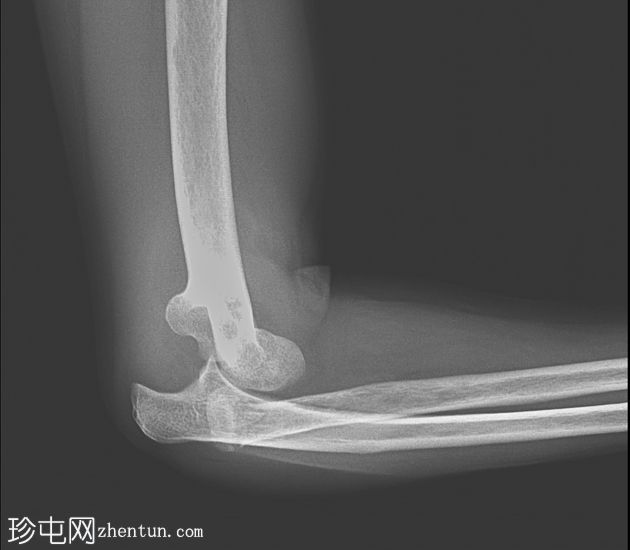

侧位

桡骨和尺骨相对于肱骨远端后脱位

桡骨颈横行骨折,桡骨头骨折块轻度移位

肱骨远端或冠突未见明显骨折

周围软组织肿胀和关节积液